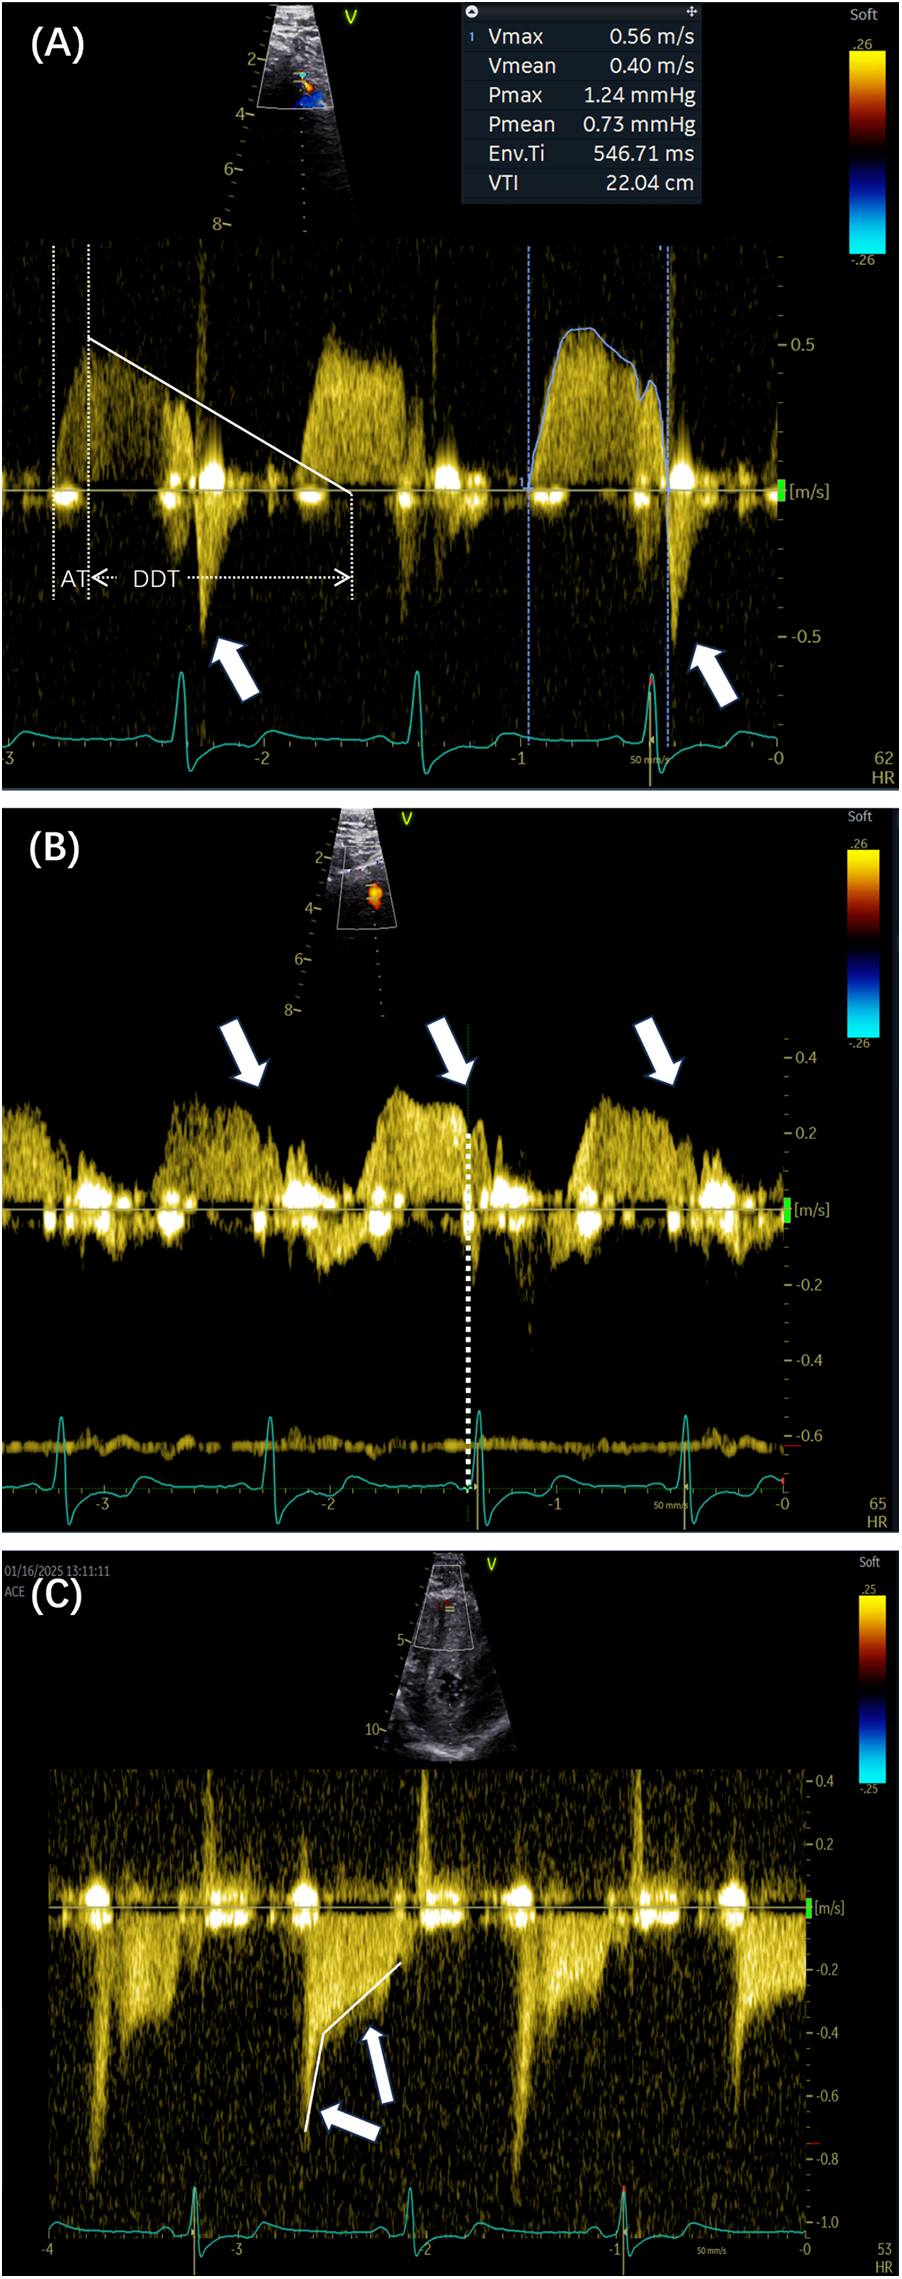

Peak flow velocity is defined as the highest instantaneous velocity within the systolic or diastolic phase, as measured from the coronary flow Doppler spectrum. The velocity is obtained by tracing the outer envelope of the Doppler signal using dedicated post-processing software, which automatically calculates the peak and mean velocities. The peak diastolic–systolic velocity ratio, peak stenotic to pre-stenotic diastolic velocity ratio, and pre-stenotic to stenotic mean diastolic flow velocity ratio are then calculated. The mosaic flow is regarded as a turbulent flow, characterized by locally persistent color aliasing due to rapid velocity exceeding the Nyquist limit. In detecting coronary stenosis, rescaling of the Nyquist limit of color flow Doppler at 0.48 m/s has been shown to be effective (15). Diastolic deceleration time (DDT) is measured from the peak diastolic velocity to the point where the initial decay slope line intersects with baseline. Diastolic pressure half-time (DPH) is the time interval required for peak diastolic velocity to decrease to of its initial value. Acceleration time (AT) refers to the time from the onset of flow to the peak velocity on the Doppler velocity curve. Systolic flow reversal (SFR) is a reversal of blood flow direction during ventricular systole, in the opposite direction to diastolic forward flow. Two unique coronary flow Doppler patterns have been identified as follows: the end-diastolic velocity sudden dip, which is caused by atrial contraction, is defined as a transient decrease in coronary flow velocity occurring between the P wave and the peak of the R wave on the electrocardiogram; and a unique square root sign is characterized by a steep velocity slope and followed by a plateau phase. Figure 2 illustrates representative parameters of these patterns.

Figure 2

(A) The outline of the Doppler spectrum was traced to calculate various parameters, including the peak velocity, mean velocity, and velocity–time integral. The white lines indicate the DDT and AT. The arrows show the presence of SFR (arrows). (B,C) Two Doppler spectrum features are indicated by the sudden dip in end-diastolic velocity (arrows) and the corresponding time point of the dip (dashed lines). The square root sign patterns are indicated by arrows. DDT, diastolic deceleration time; AT, acceleration time; SFR, systolic flow reversal.